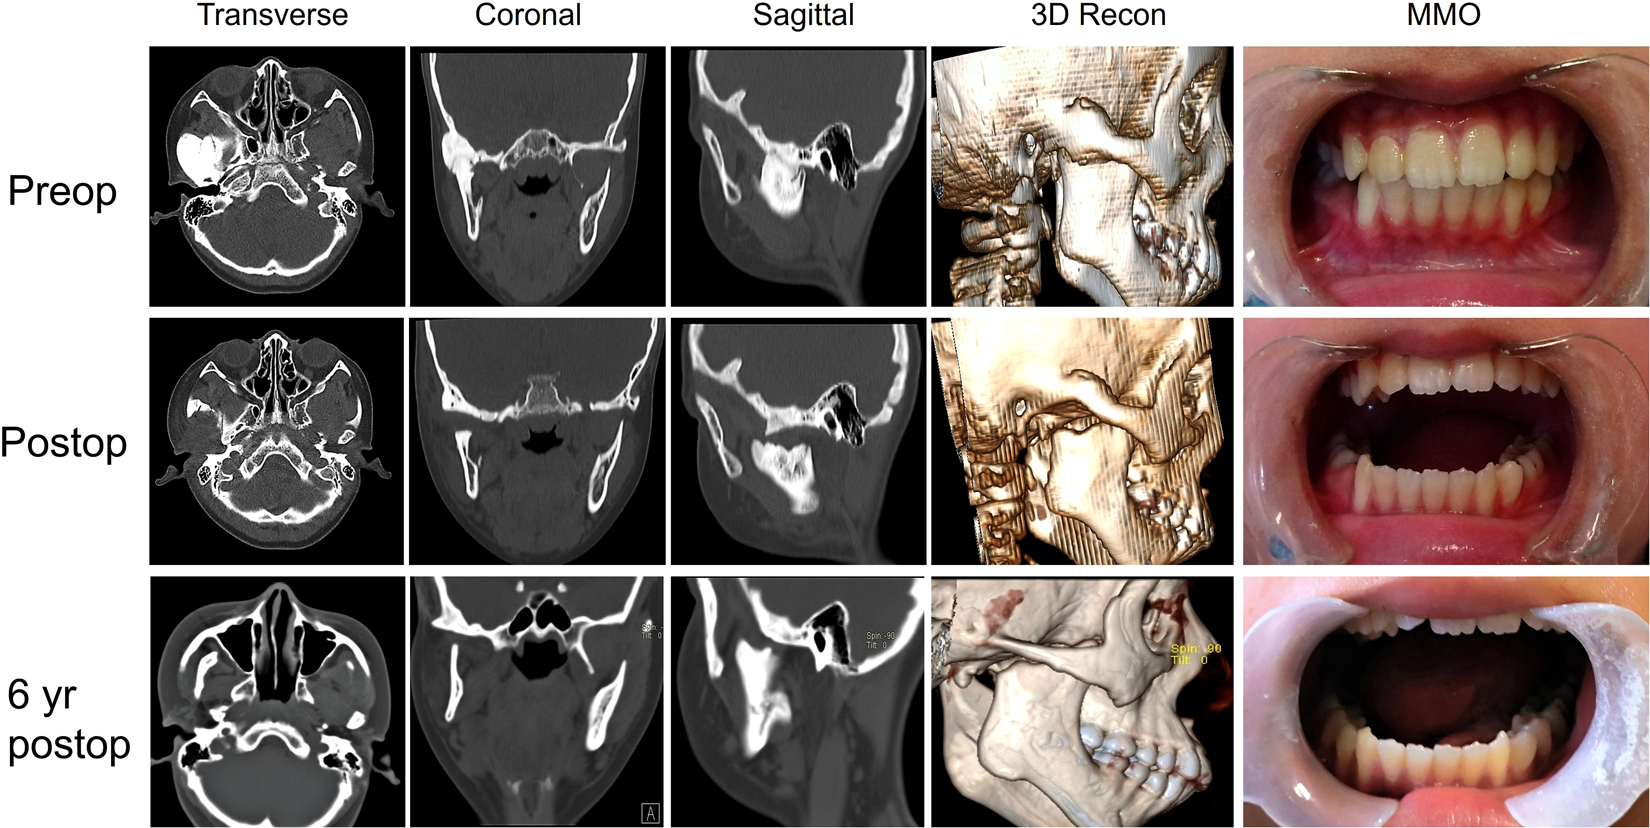

Figure 2

Preoperative, postoperative and 6 years postoperative follow-up CT scan and MMO showed a substantial reduction of the ankylotic block and stable improvement of MMO. (a) Preoperative transverse CT scan; (b) preoperative coronal CT scan; (c) preoperative sagittal CT scan; (d) preoperative 3D reconstruction of CT scans; (e) preoperative MMO; (f) postoperative transverse CT scan; (g) postoperative coronal CT scan; (h) postoperative preoperative sagittal CT scan; (i) postoperative 3D reconstruction of CT scans; (j) postoperative MMO; (k) 6 years postoperative transverse CT scan; (l) 6 years postoperative coronal CT scan; (m) 6 years postoperative sagittal CT scan; (n) 6 years postoperative 3D reconstruction of CT scans; (o) 6 years postoperative MMO.